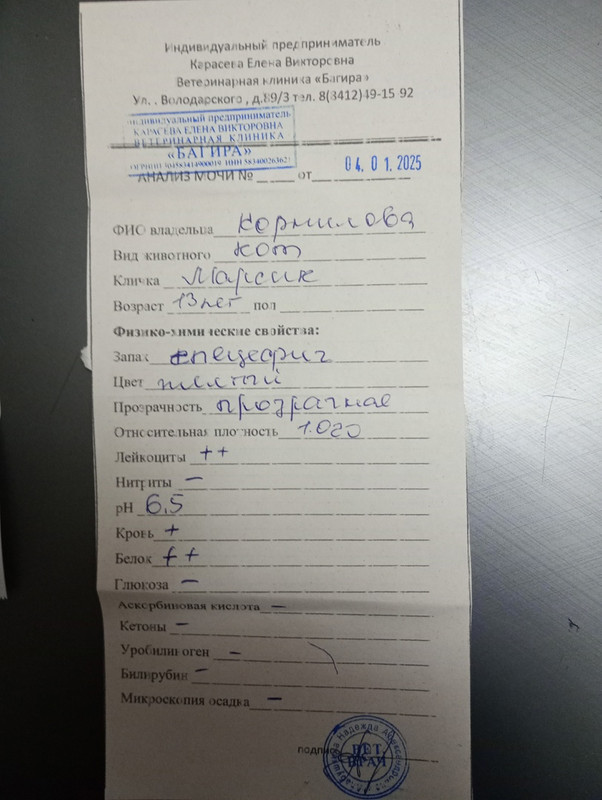

Общий анализ мочи

Общий анализ мочи

Общий анализ мочи

Общий анализ мочи